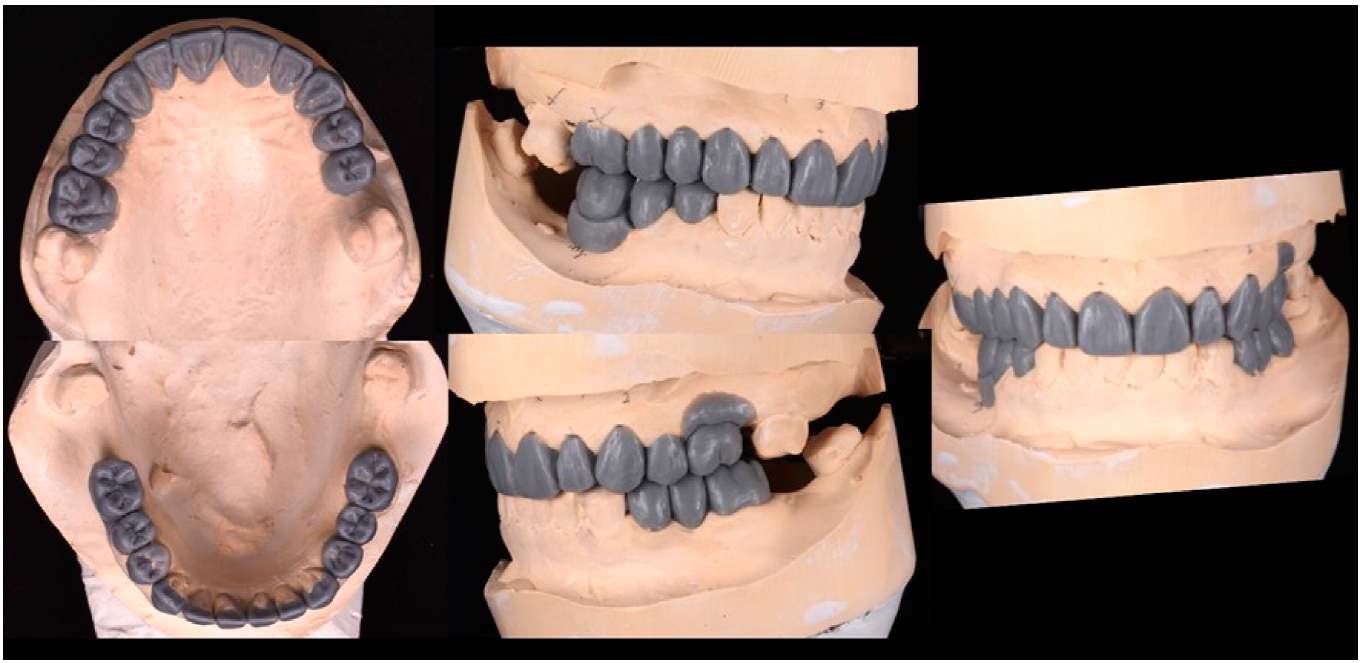

El plan de tratamiento se dividió en cuatro fases, Fase 1: se tomaron fotografías, radiografías, modelos de estudio y se realizó un encerado para determinar diagnóstico, pronóstico y plan de tratamiento (Figura 2. A). Además, se realizó fase 1 periodontal para retirar focos de infección. En la Fase 2 se retiraron todas las coronas de metal porcelana presentes en boca y se colocaron provisionales de acrílico de la misma forma y altura de las coronas que la paciente presentaba, esto con el fin de observar el estado de los dientes remanentes. Posteriormente se realizó el tratamiento de conductos del diente 15. Después se llevó a cabo la planeación digital de diseño de sonrisa propuesta por Coachman et al.13, mediante el cual se obtuvieron parámetros para realizar un encerado de diagnóstico realizando un mock-up de prueba para determinar la nueva DVO de la paciente, proyectando un aumento de 3mm (Figura 3. A).